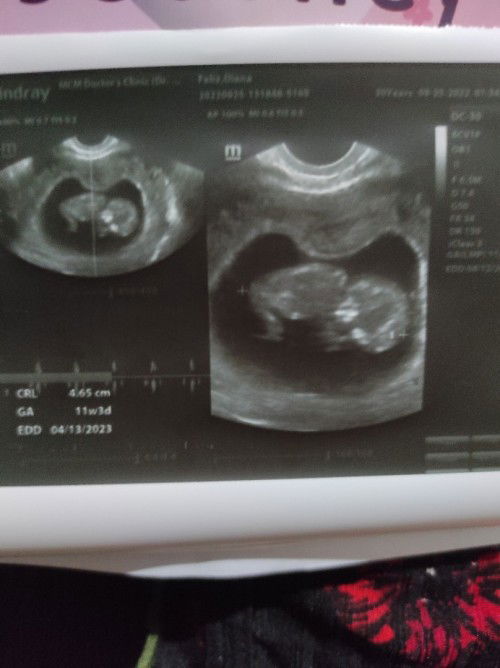

Okay lang po kaya na nakadapa si baby? At magbabago pa kaya posisyon nya? Salamat po.

11wks 3days first time mom

magbabago pa po yan recommend ni Doc dapat left side ka matulog para umikot sya kasi pag nakatihaya ka magalaw talaga sya nun

normal po yan sa ganyang mga gestational age. magbabago pa po yan